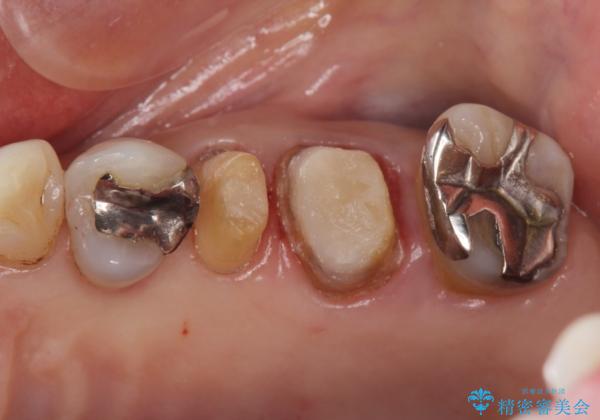

70代女性 段差のある被せ物のやり替え

- 左下の大臼歯(6番)の根の治療を行いました。

後方の歯が欠損していた為、インプラントをお勧めしましたが希望されませんでした。

その代わり、現在ある歯をしっかり治療することになり、左上下の治療を行っています。

左下6番の根管治療は六本木院の林院長にお願いしています。